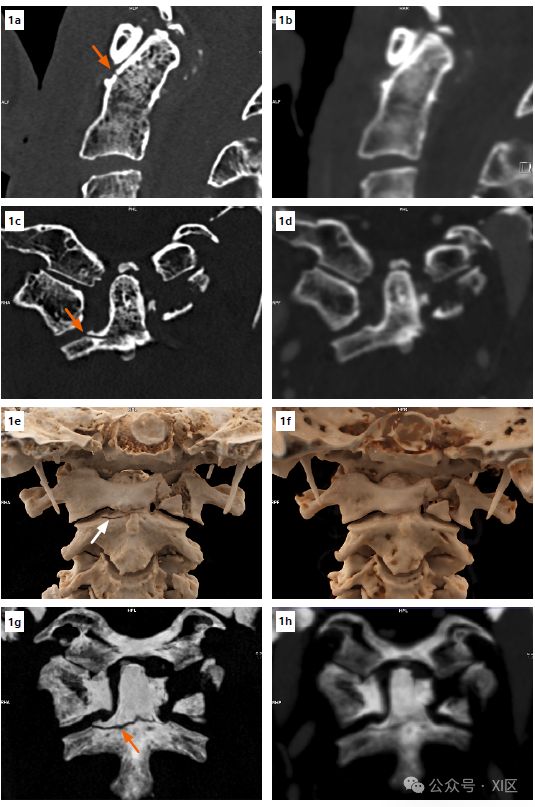

患者男, 65 岁,外伤。能量积分探测器 (EID) CT显示颈椎多处骨折。 24 小时后,使用单源光子计数探测器 (PCD) CT进行复查。PCD CT图像显示:C2齿状突底部有一个非移位不稳定骨折,之前EID CT图像没有发现的。左边一列为PCCT,右边一列为EID-CT。